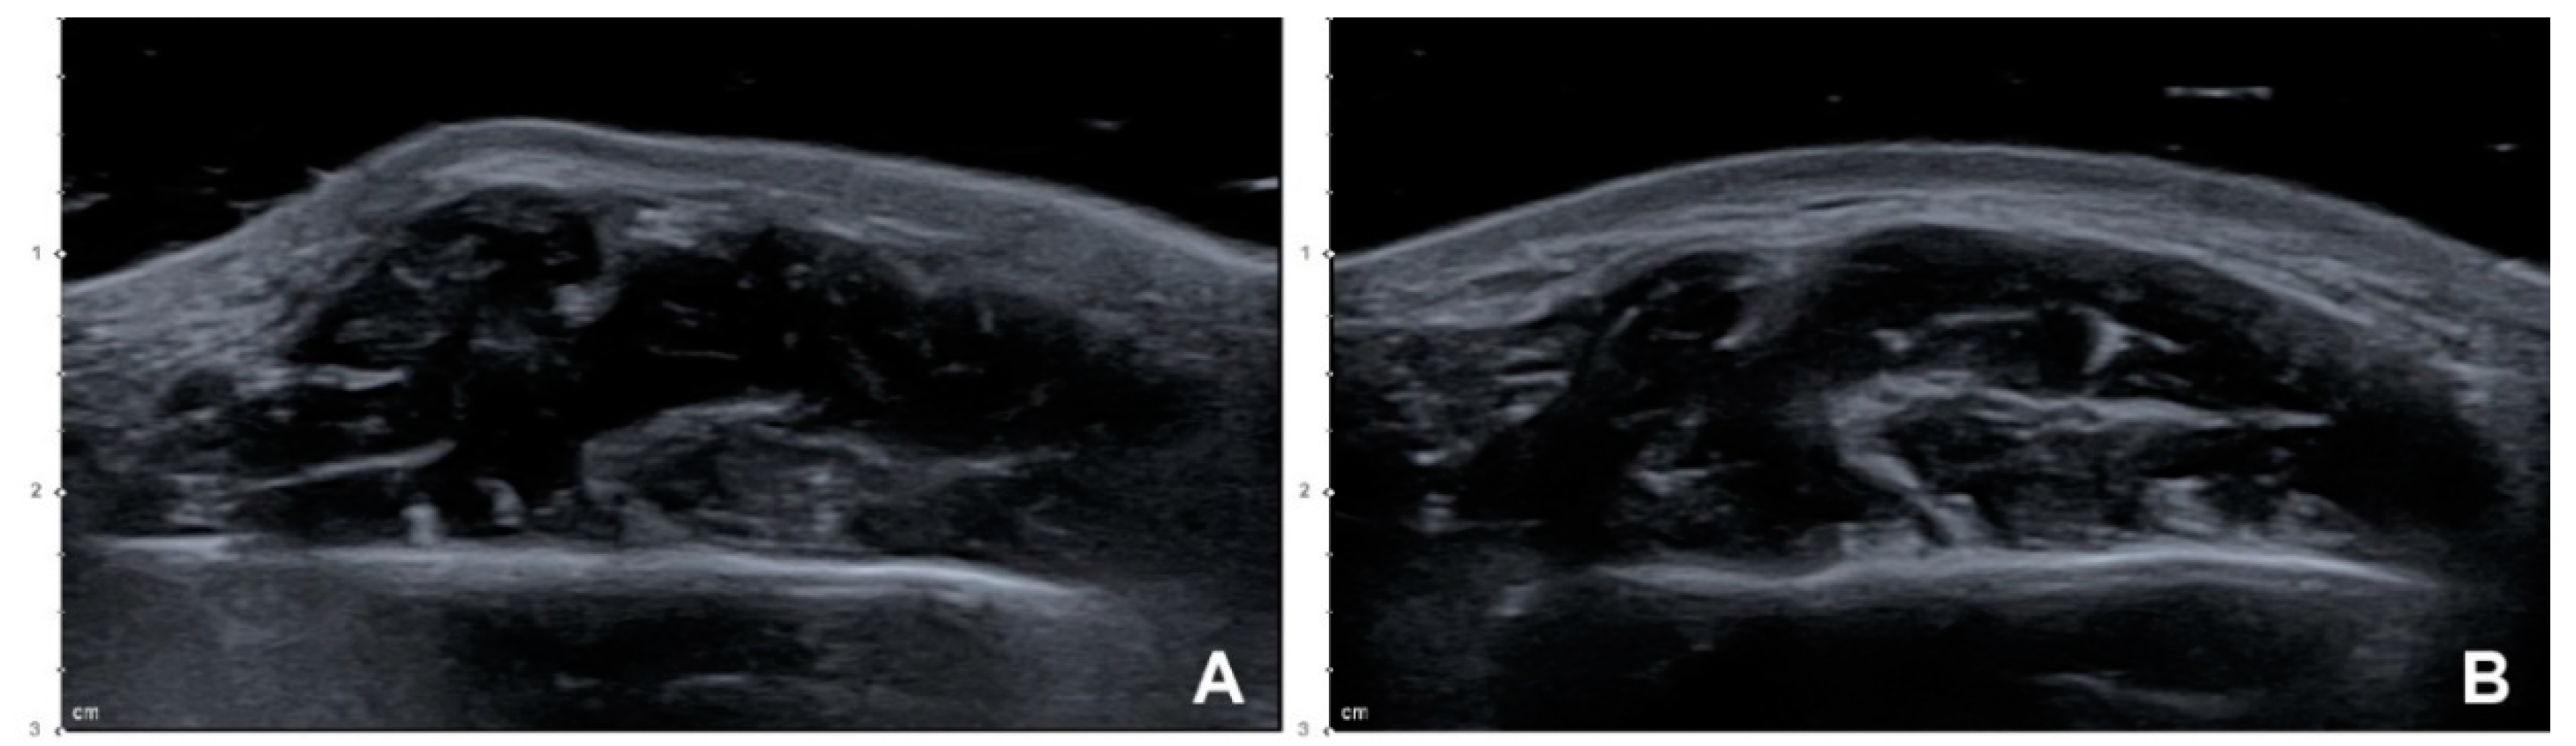

Figure 2.

Ultrasonography (US) images of PMB after performing the conventional blind injection: (A) Superficial part of the masseter showing localized excessive contraction while clenching (B mode, transverse view, 15-MHz linear transducer); (B) localized excessive contraction in the clenching state was resolved after performing a compensational injection of 8 U of BoNT-A into the superficial part of the masseter (B mode, transverse view, 15-MHz linear transducer).